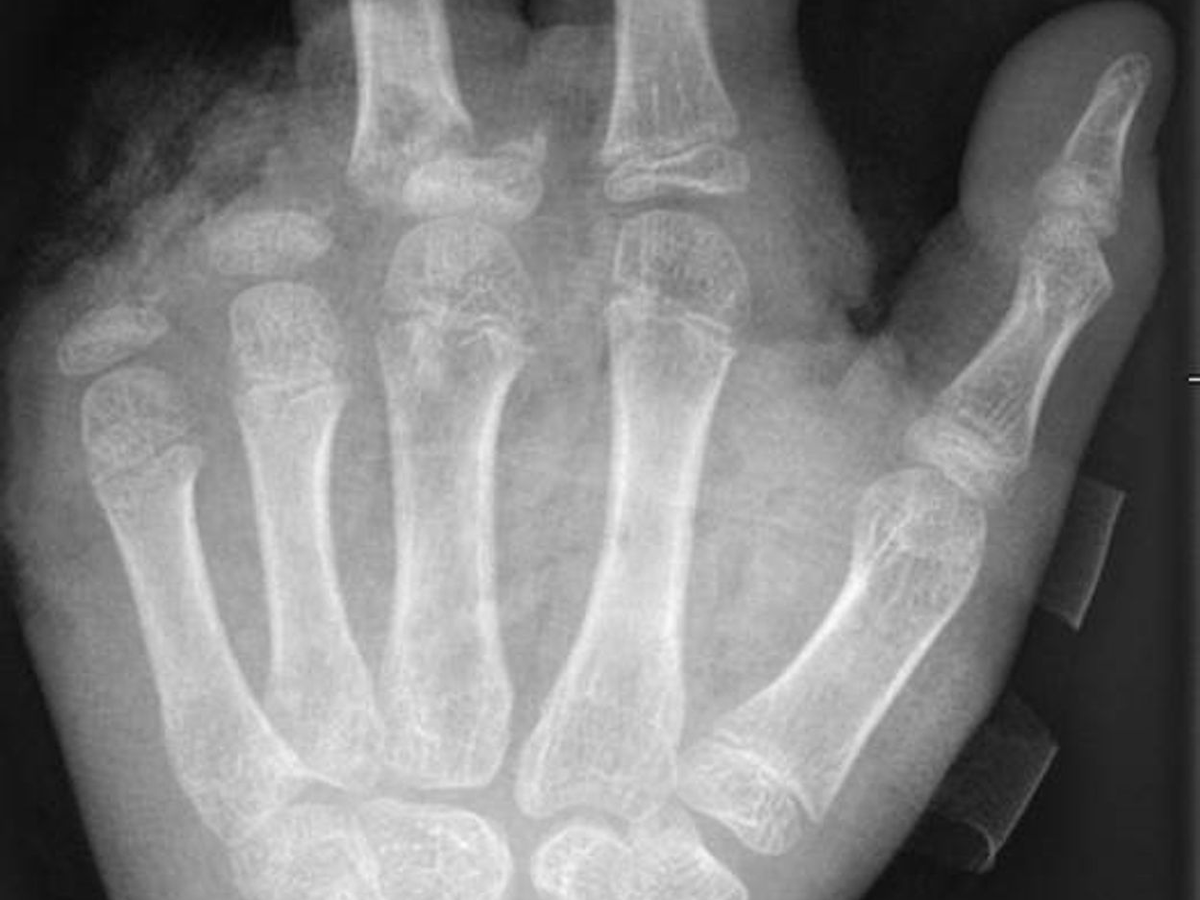

In der Handchirurgie müssten an Silvester im Unfallkrankenhaus rund 20 bis 40 Menschen mit Böllerverletzungen operiert werden, sagt die Ärztin. Dieses Jahr werde sie mir vier weiteren Handchirurgen im Einsatz sein. Die häufigsten Verletzungen entstünden durch explodierende Böller in der Hand.

«Der überwiegende Teil der Verletzungen trägt tatsächlich lebenslange Folgen mit sich, weil die Sprengkraft dazu führt, dass eben nicht nur einzelne Strukturen verletzt sind, sondern immer mehrere. Und das heilt praktisch nie ganz folgenlos ab.» Zum Teil könnten Hände nicht mehr gerettet und müssten amputiert werden.

Für eine neue Dimension habe im vergangenen Jahr das illegale Abbrennen von Kugelbomben gesorgt. «Die Patienten mit Verletzungen durch Kugelbomben weisen sehr viel stärkere Verletzungsmuster auf, die auch den ganzen Körper betreffen, weil diese Explosion ungerichtet stattfindet. Und das sind nicht nur Hände und Gesichter, sondern auch Bauch, Beine.» Alle Körperareale seien gleichermaßen gefährdet.